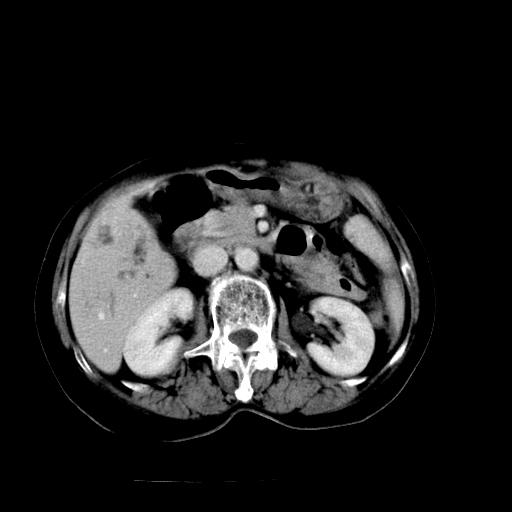

以下是引用随光逐影在2009-4-7 8:21:00的发言:[br]肝内外胆管多发性结石并肝内外胆管扩张;胆系感染。